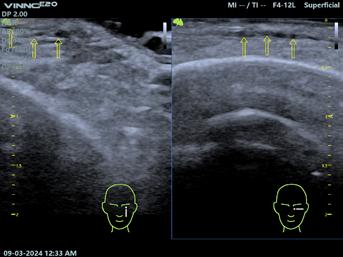

Fig.2. Ecocardiografie transtoracică – pacient sever simptomatic cu cardiomiopatie hipertrofică. (A) Sept interventricular cu hipertrofie extremă. (B) Mișcare sistolică anterioară a valvei mitrale (SAM) și contact mitro-septal. (C) Contact mitro-septal prelungit în timpul sistolei (mod M). (D) Gradient de circa 130 mmHg în tractul de ejecție al ventriculului stâng (Doppler). Adaptat după [15]

Principala metoda imagistică de evaluare și monitorizare a pacienților cu CMH este ecocardiografia bidimensională (2D).

Este esențial ca evaluările ecocardiografice să fie făcute diligent și după un protocol standard, orientarea și alinierea în planuri ortogonale trebuie să fie corecte pentru a măsura corespunzător structurile cardiace. Protocolul standard este util mai ales pentru că hipertrofia din CMH, deși interesează cel mai frecvent septul bazal, poate interesa orice segment ventricular (SIV posterior, apex VS, perete lateral)[12]. Se urmăresc parametri ca funcția sistolică și diastolică a VS, hipertrofia VS, prezența sau absența obstrucției în TEVS, volumul atriului stâng (AS), precum și date despre morfologia și funcția aparatului mitral.

Estimarea grosimii peretelui VS se face din mai multe incidențe, la sfârșitul diastolei, în secțiuni ax scurt, evitând secțiunile oblice care supraestimează hipertrofia ventriculară. Secțiunea parasternală ax lung, în modul M, ar trebui evitată pentru efectuarea măsurătorilor[13]

Conform ghidurilor de specialitate, tuturor pacienților diagnosticați cu CMH le este recomandată efectuarea ecocardiografiei 2D și Doppler, atât în repaus, cât și în timpul manevrei Valsalva – dacă gradientul de repaus este sub 50 mmHg și pacientul este simptomatic.

În cadrul urmăririi cardiologice de rutină, parte a îngrijirii optime este efectuarea de ecocardiografii transtoracice seriate. La pacienții asimptomatici, ETT se recomandă a fi repetată o dată la 1-2 ani, urmărindu-se modificări ale funcției sistolice și diastolice a VS, gradul de hipertrofie, obstrucția din TEVS, boli valvulare concomitente. Intervalul ar putea fi extins dacă pacientul rămâne clinic stabil după multiple evaluări[6]

Fiziopatologia care contribuie la obstrucția TEVS (Fig.2) include anomalii interconectate precum hipertrofia asimetrică a VS, SAM, hipertrofia mușchilor papilari cu sau fără deplasarea acestora, inserții anormale ale mușchilor papilari, cât și modificări la nivelul cuspelor valvei mitrale (VM)[14]

Fig.3. Ecocardiografie transesofagiană în cardiomiopatie hipertrofică obstructivă, ce remarcă obstrucția tractului de ejecție al ventriculului stâng (VS) prin contact mitro-septal (sus, săgeată) și regurgitare mitrală importantă (jos) ETE efectuată perioperator (Fig.3) este însă esențială pentru ghidarea strategiei chirurgicale în cazul miectomiei chirurgicale,